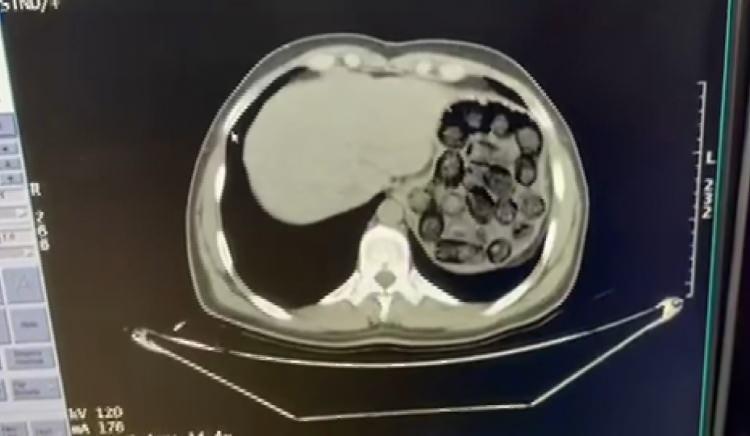

Midelerinden çıktı: Diyarbakır'da inanılmaz operasyon

İRAN'DAN TÜRKİYE'YE UYUŞTURUCU SEVKİYATI

İl Emniyet Müdürlüğü Narkotik Suçlarla Mücadele Şube Müdürlüğü ekipleri, İran'dan Türkiye'ye farklı bir yöntemle uyuşturucu getirileceğini tespit etti.